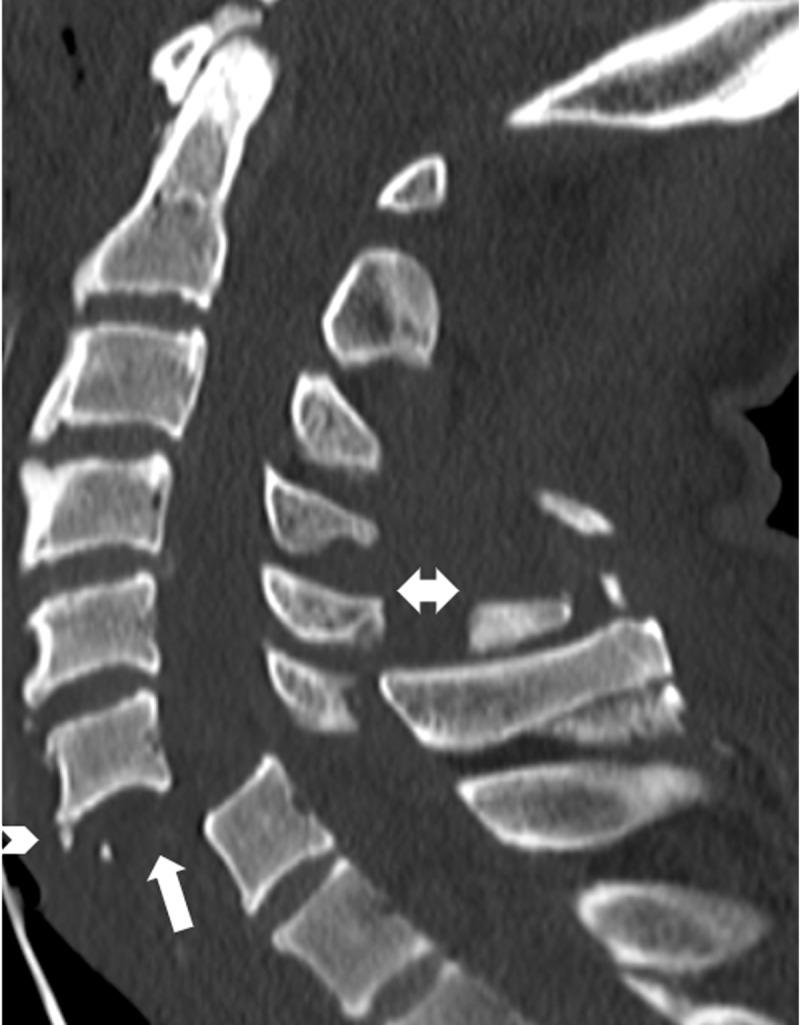

Unilateral cervical facet joint dislocation (UCFJD) is the most frequently missed cervical spine injury on plain radiographs. If left untreated, UCFJD can progress to bilateral cervical facet joint dislocation. Given the complexity of cervical facet joint dislocations, radiologists rely on metaphorical signs to identify them on radiographs. The "Bow-tie" and "laminar space" signs represent UCFJD on plain radiographs. The "reversed hamburger", "naked facet" and "headphones" signs represent cervical facet joint dislocations on axial cross-sectional imaging. Illustrating these signs in an engaging manner facilitates pattern-based recognition, which can benefit trainees and radiologists. Moreover, pattern-based recognition can be applied to machine learning.

单侧颈椎小关节脱位(UCFJD)是普通X线片上最常被漏诊的颈椎损伤。如果不进行治疗,UCFJD可进展为双侧颈椎小关节脱位。鉴于颈椎小关节脱位的复杂性,放射科医生依靠隐喻性征象在X线片上识别它们。“领结”和“椎板间隙”征象在普通X线片上代表UCFJD。“反转汉堡包”、“裸关节面”和“耳机”征象在轴向横断面成像上代表颈椎小关节脱位。以引人入胜的方式展示这些征象有助于基于模式的识别,这对实习生和放射科医生都有益。此外,基于模式的识别可应用于机器学习。